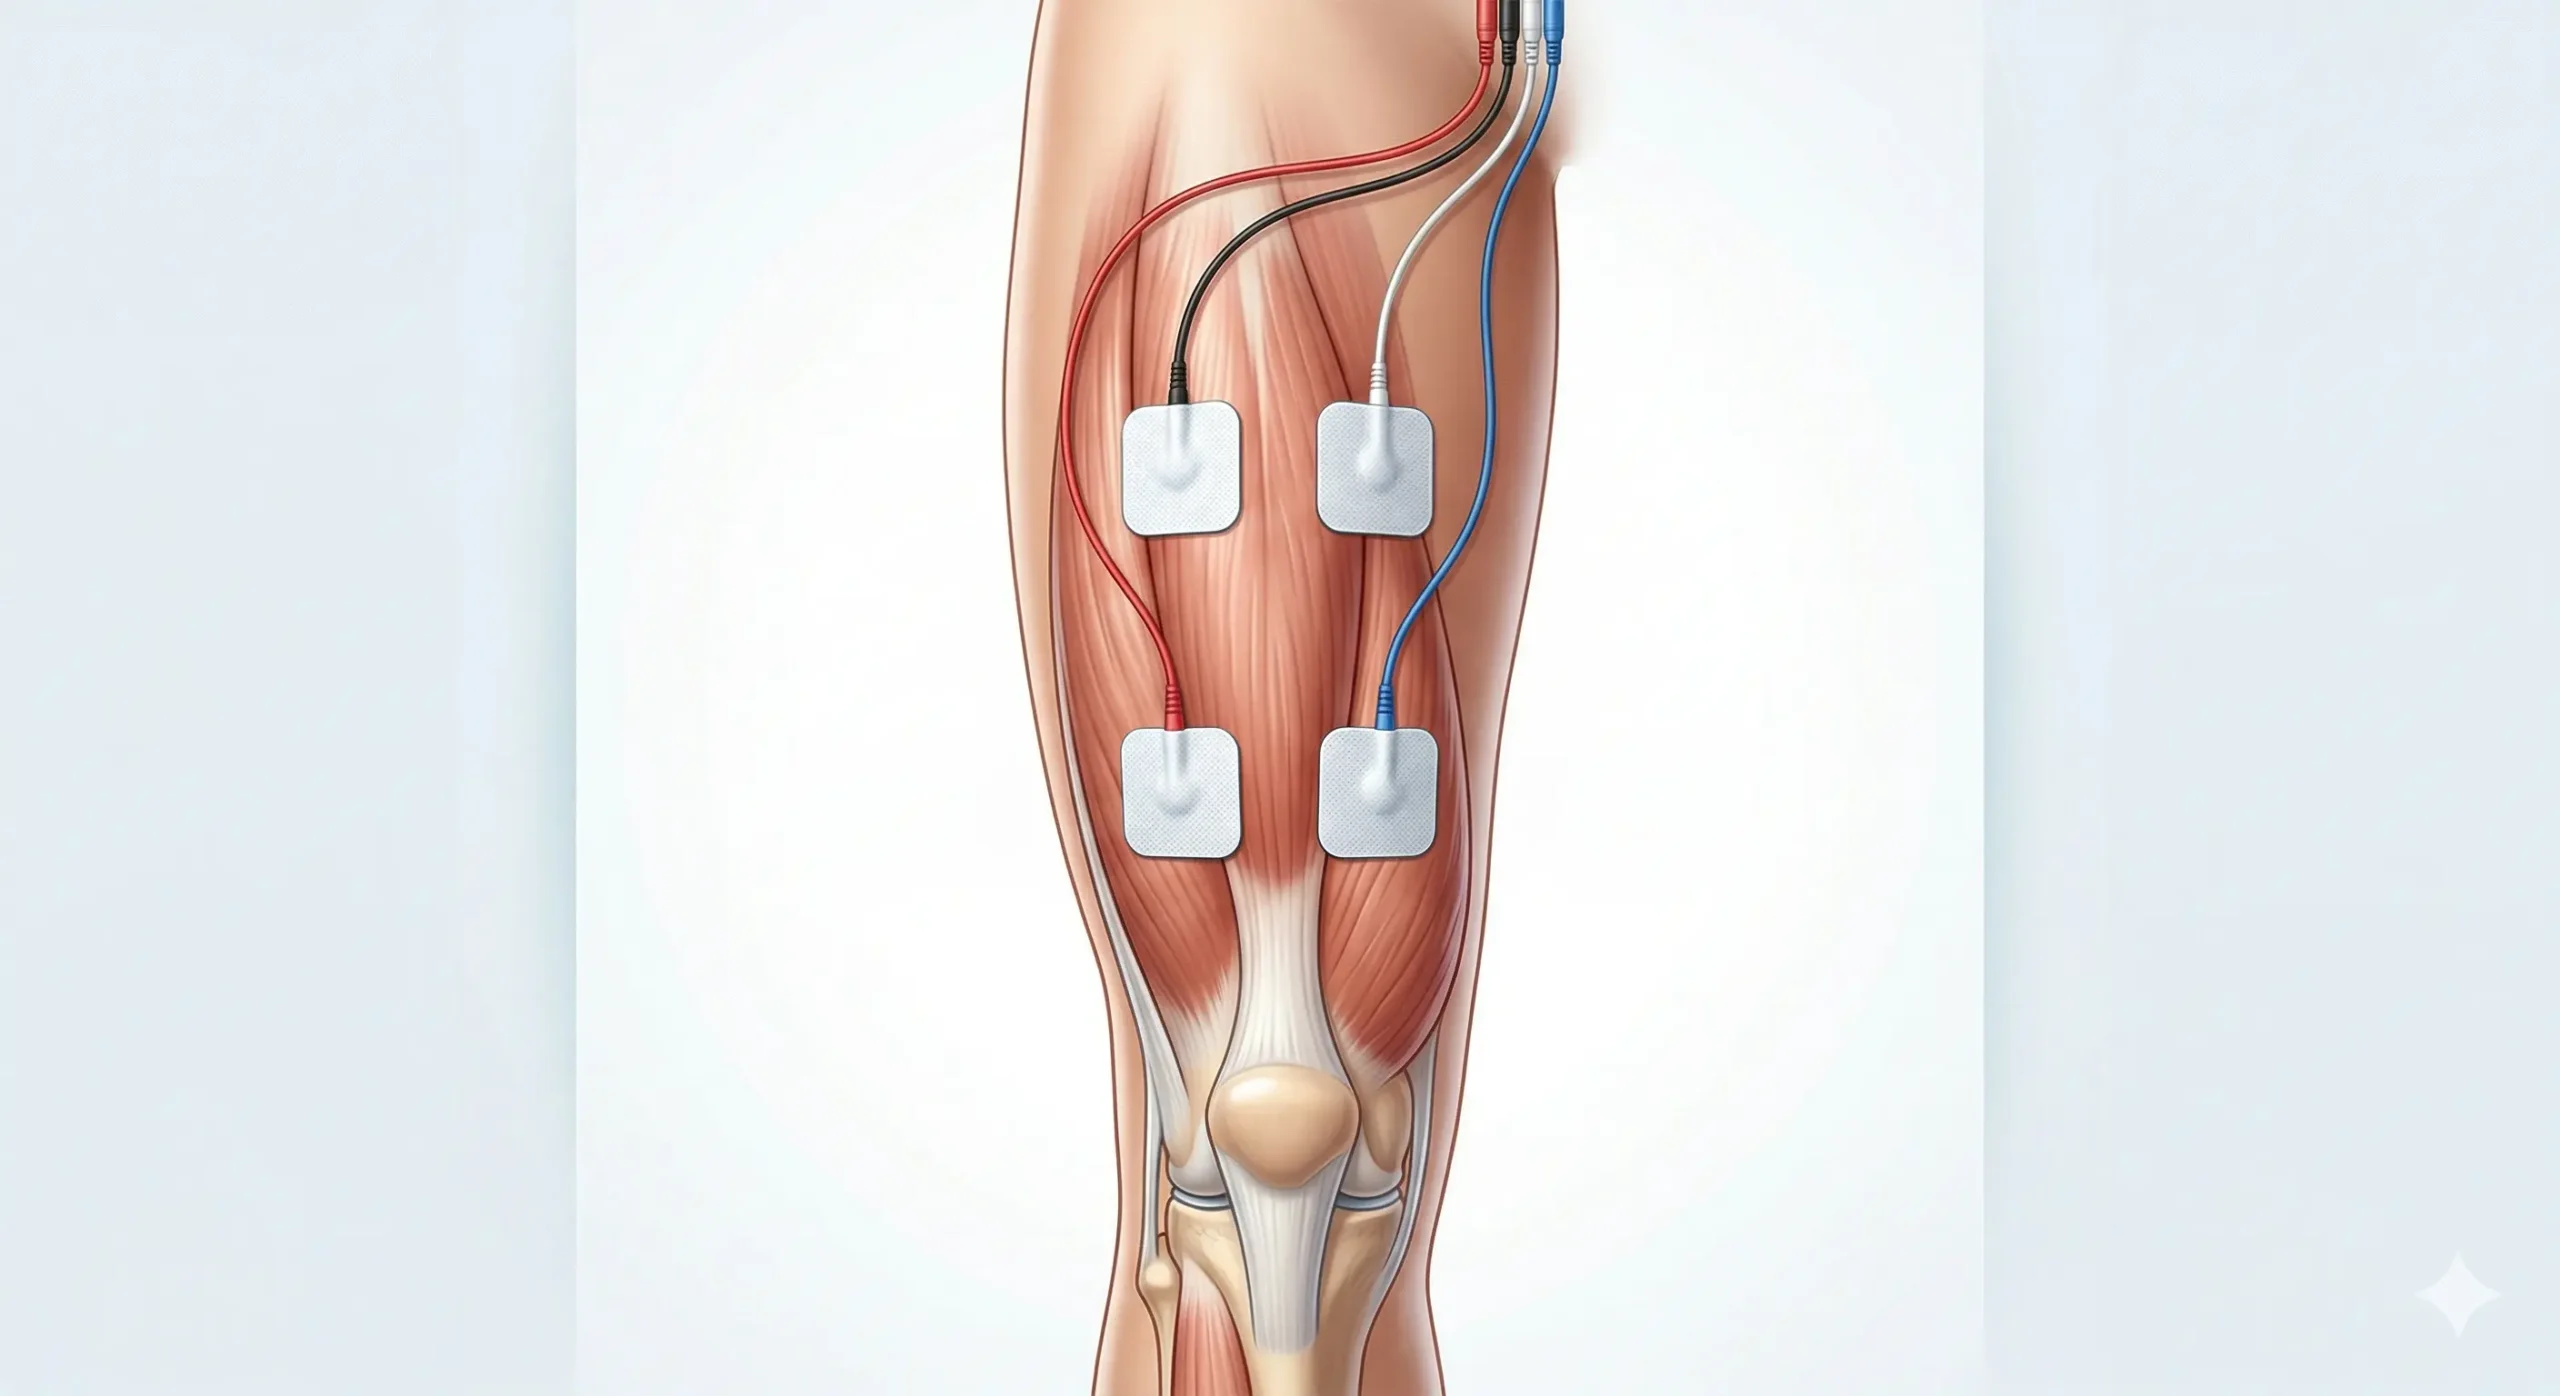

Imágenes de colocación del TENS en cuádriceps

A) Imagen: TENS en cuádriceps

Este montaje es el más útil cuando la molestia está repartida por el muslo anterior. Coloca los electrodos sobre la masa muscular y evita la rótula.